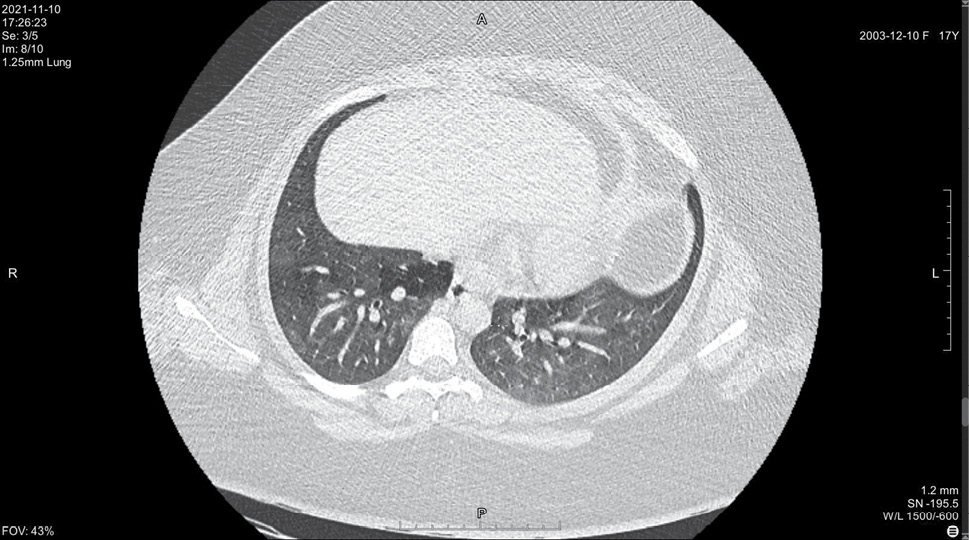

На 14 день болезни (10.11, 7 день госпитализации) была выполнена спиральная компьютерная томография грудной клетки, где выявлены признаки двусторонней интерстициальной полисегментарной пневмонии (рис. 1–8). Форма грудной клетки описана как обычная. Легочные поля расправлены. На томограммах бронхиальное дерево визуализировано до субсегментов: сами бронхи не деформированы, их просвет в пределах нормы, устья свободны, проходимость сохранена на всем протяжении. Во всех сегментах с обоих сторон определялись полиморфные, сливные участки уплотнения легочной ткани по типу матового стекла с участками консолидации. На этом фоне были видны просветы бронхов. Определялись фиброзные тяжи в проекции апикальной плевры обоих легких. Контуры диафрагмы четкие, синусы свободные, свободная жидкость в плевральной полости отсутствовала. Трахея обычной формы и размеров, карина острая. Сосудистые структуры верхнего средостения с четкими контурами и нормального диаметра, стенки сосудов без кальцинатов. Медиастинальные лимфоузлы и лимфоузлы корней обоих легких (без контрастного усиления) визуализированы единично, не увеличены. Сердце расположено обычно, размеры в пределах нормы. Выявлены умеренные дегенеративно-дистрофические изменения грудного отдела позвоночника. Мягкие ткани грудной клетки без особенностей. По заключению врача-рентгенолога, объем пораженной легочной паренхимы достигал 95%. Наиболее вероятно, что патологический процесс у пациентки имел вирусную природу.

Рисунок 6. Томограмма легких на уровне ThVIII

Рисунок 7. Томограмма легких на уровне ThIX